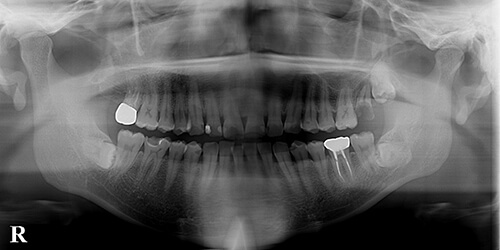

【治療前】

左上7(第2大臼歯)が歯冠崩壊して残根状態で保存不可能と思われますが、その下に未萌出の8(親知らず)が確認できます。